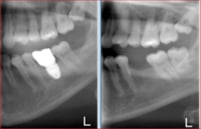

55 years old male had lost posterior teeth in all 4 quadrants, had collapsed bite with moderate TMJ arthrosis.

Dr. Andrews performed a SINGLE surgery – 7 implants placed along with few extractions and bi-lateral crestal sinus lifts.

Restored 100% digitally, utilizing CAD-CAM technologies, all screw-retained full contour zirconia implant crowns with life-time warranty for breaking/chipping.

Collapsed bite had been opened with Gneuromuscular technique. Occlusion was equilibrated 2 weeks after delivery with TENS. Cavities on front teeth were filled with tooth-colored composite fillings.